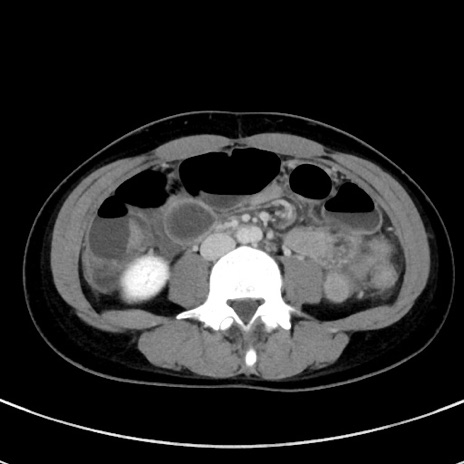

冠状断像

【症例】20歳代女性

【主訴】嘔吐、下腹部痛

【現病歴】昨日夕食後に嘔吐し下腹部痛が出現。本日になっても嘔吐持続し改善しないため来院。

【身体所見】意識清明、BT 37.2℃、BP 108/67mmHg、腹部:平坦、やや硬、下腹部正中から右にかけて圧痛あり、反跳痛軽度あり、tapping pain(+)。

【データ】WBC 13600、CRP 14.94